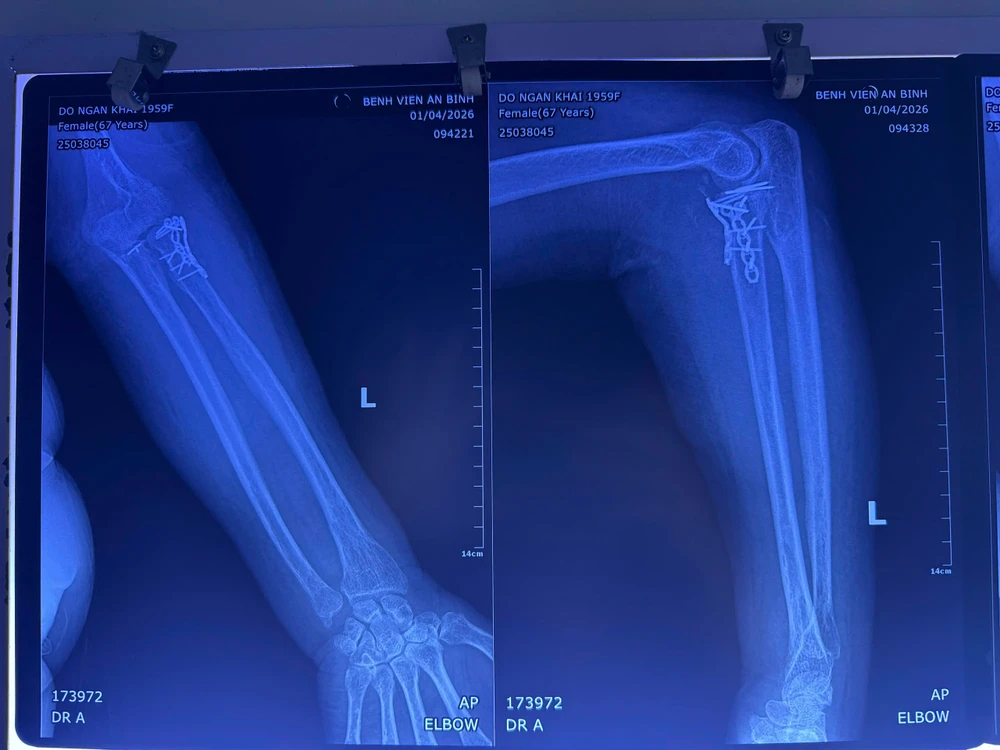

Trường hợp thứ nhất, bệnh nhân bị tam chứng đau khổ (tình trạng tổn thương phức tạp gồm gãy mỏm vẹt xương trụ, chỏm xương quay, trật khớp khuỷu). Ngoài ra bệnh nhân còn mắc nhiều bệnh lý nền như tăng huyết áp, đái tháo đường, loãng xương, cushing.

Bệnh nhân được xử trí kết hợp xương quay bằng nẹp vít, kết hợp xương mỏm vẹt xương trụ bằng kim Kirschner, khâu đính lại điểm bám dây chằng bên ngoài.

Hình chụp phim bệnh nhân bị gãy xương phức tạp kèm trật khớp. Ảnh: BVCC

Trường hợp thứ 2, bệnh nhân bị gãy hở độ II nhiều mảnh liên lồi cầu xương cánh tay kèm gãy 1/3 dưới, trật khớp quay trụ dưới cùng bên trái, tăng huyết áp, đái tháo đường.

Bệnh nhân được xử trí thành hai thì. Thì 1 là mổ cấp cứu cắt lọc, cố định bằng nẹp bột tránh nguy cơ nhiễm trùng; thì 2 là điều trị thực thụ như kết hợp liên lồi cầu xương cánh tay bằng nẹp vít, kết hợp xương quay bằng nẹp vít, cố định khớp quay trụ dưới bằng kim Kirschner.